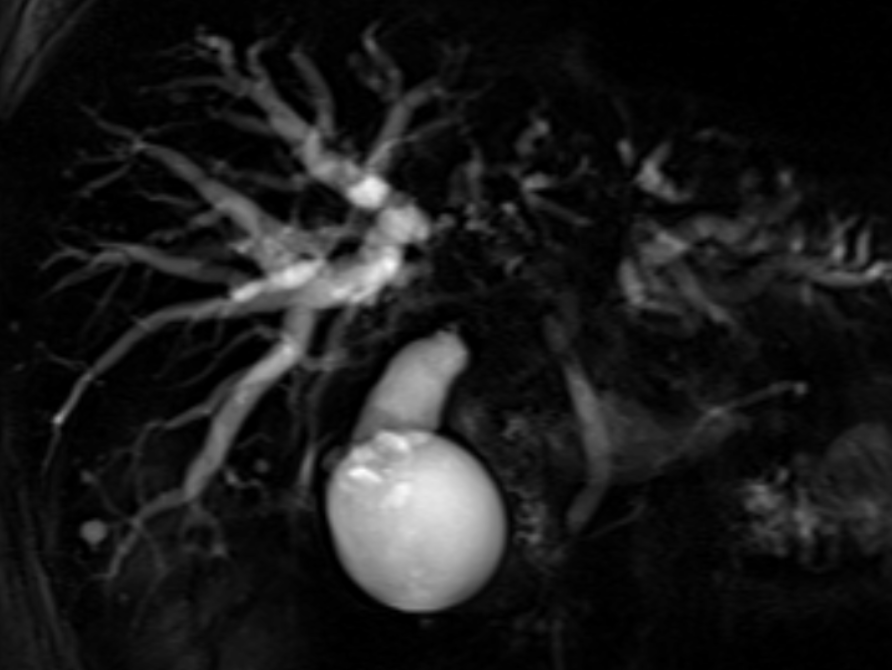

入院后,科室团队完善 MRCP 等检查,全面评估肿瘤侵犯范围及肝功能储备,排除内镜手术禁忌。经全科术前讨论,结合国际最新临床研究进展[1]及患者实际情况,制定个性化内镜微创方案。在充分告知病情、治疗方案、预期疗效及风险后,团队为患者实施内镜下胆管活检+超细外鞘胆管双金属支架同步置入术。手术在透视引导下精准完成导丝超选互不交通的右前及右后肝内胆管、胆管活检、两根超细外鞘胆管金属支架同步置入等关键步骤。术后患者康复顺利,黄疸明显下降,未出现ERCP相关并发症。

术前影像学评估:高质量磁共振胰胆管成像(MRCP)是评估肝门部胆管狭窄形态、长度、上游胆管扩张程度及分支胆管角度的重要依据。ERCP术中应避免过度造影导致互不交通的多支肝内胆管分支显影,若无法实现充分引流,则可能诱发难以控制的胆管炎[2]。应尽可能在ERCP操作前完成高质量的MRCP检查,根据MRCP图像进行精准超选,精准引流目标胆管并且避免非目标胆管的显影。